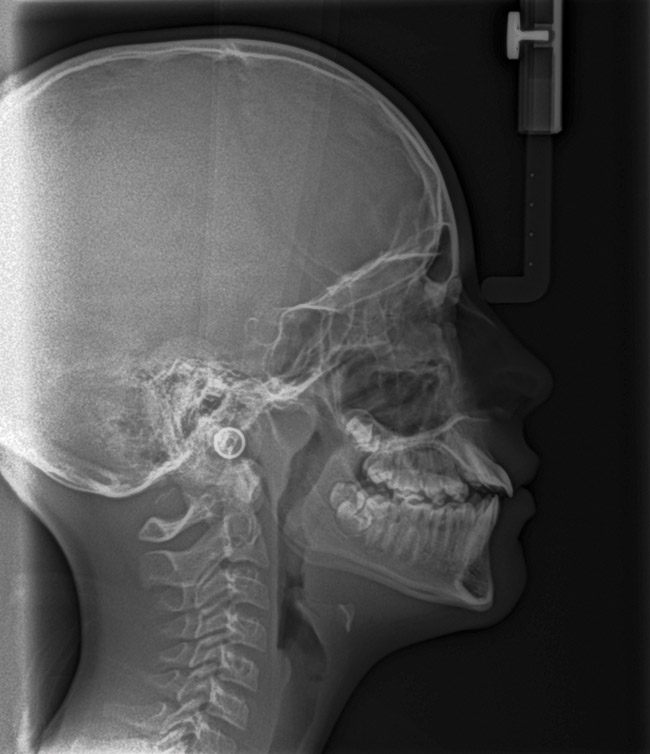

(15.) Cephalometric evaluation demonstrates significant tonsillar blockage of the airway and bimaxillary retursion.

Figure 15